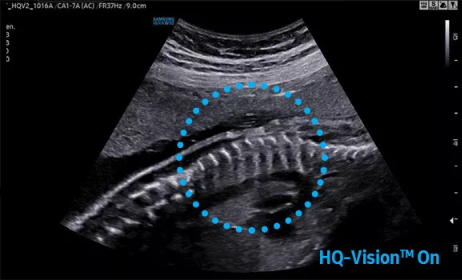

2D成像方面,Hera i10集成了包括ShadowHDR?、HQ-Vision?、ClearVision等多項(xiàng)具有三星“血統(tǒng)”的技術(shù),加強(qiáng)了圖像的陰影抑制、減少偽影、緩和模糊區(qū)。